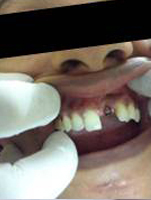

Pre Operation

Use of Bone Graft & GTR membrane for an Implant